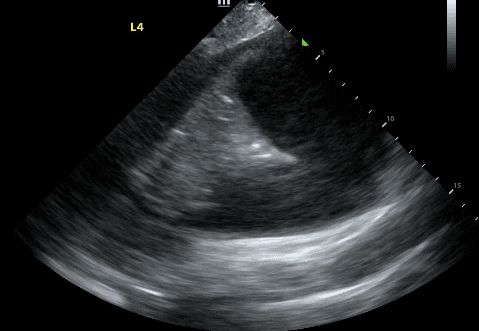

In an ideal situation, pleural effusion evaluation should take place with the patient in a seated position. This allows fluid to collect at the bottom of the lung, making it easier to detect. When a seated position cannot be achieved, place the patient in a supine position with the head of the bed between 30-45 degrees. This is referred to as the “semi-recumbent” position.

With the probe marker pointing toward the patient’s head, place the probe in the anterior axillary line, at the level of the xiphoid process. If the patient is seated, you can also move the probe posteriorly onto the patient’s back but keep it at the same horizontal level as the xiphoid process.

Next, identify the patient’s liver (if your probe is on the right side) or spleen (if your probe is on the left side). Above that, you will see a thin, hyperechoic line which is the patient’s diaphragm.